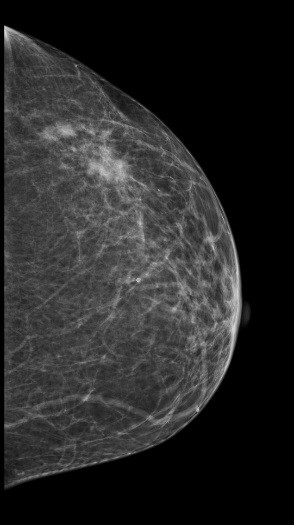

病史:患者,女,59岁,左乳肿块2月余。

2D图像:

常规2D图像MLO位和CC位外上象限见局限密度增高影,其内似见钙化影,在DBT的薄层图像上观察病变范围比2D图像的范围要大些,病变周边见长短不一毛刺,其内见多个细点样钙化影。

左乳局限致密伴钙化,BI-RADS 4C 。